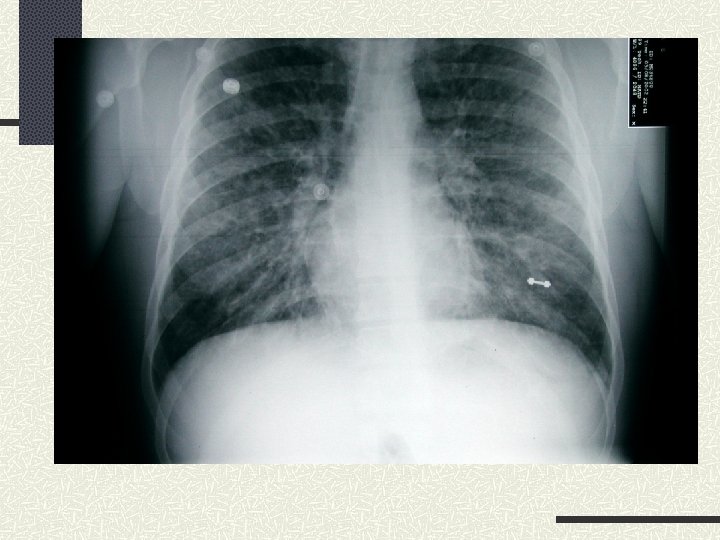

What We Know Physical Exam Afebrile n Tachycardic and tachypneic n Hypoxic n n O 2 n saturation 82% on RA and 91% on 100% NRB Abnormals n RR-30

What We Know CV – Tachycardic but no rubs or murmurs (gallop? ) Neck - ? JVD Lungs – Diffuse rales bilaterally Extremities – Track marks in the left antecubital fossa and tattoos on chest and arms

Clinical Picture Due to: Noncardiogenic Pulmonary Edema Cardiogenic Pulmonary Edema/Myocardial Infarction/Cardiomyopathy/Endocarditis/Valve or leaflet rupture Aspiration Pneumonitis Toxic Inhalants Myocardial Depressant Effects of Toxin Talc Emboli

Cardiogenic versus Noncardiogenic Pulmonary Edema (NCPE) Cephalization of Pulmonary Vessels Cardiomegaly Pulmonary Capillary Wedge Pressure > 20 mm Hg NCPE sometimes classified with ARDS